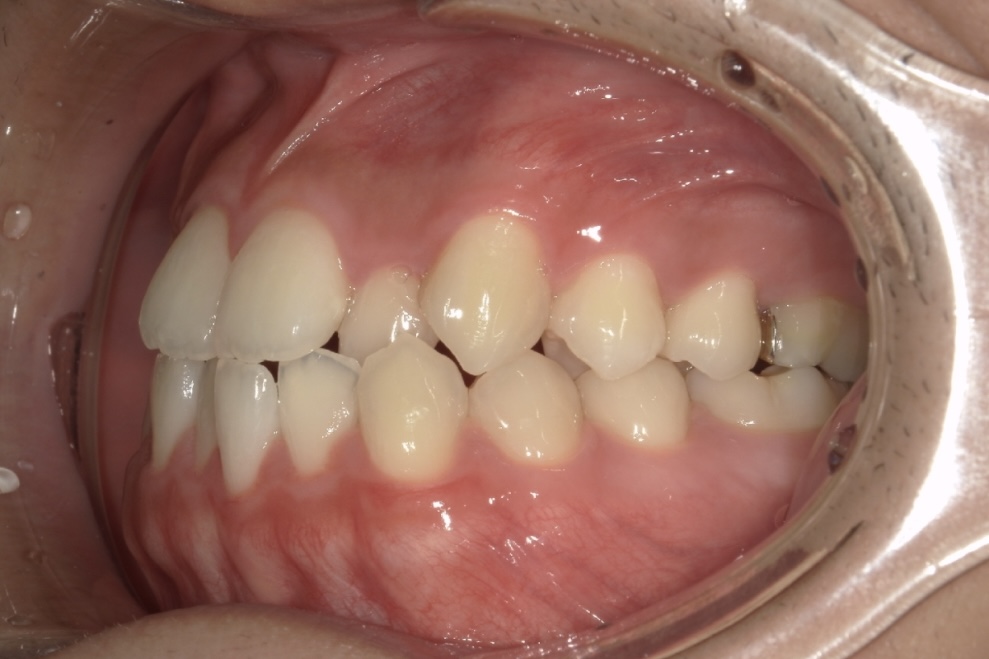

Before 2

After 2